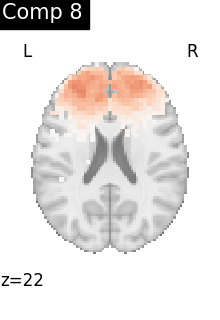

One plot of each component

for i, cur_img in enumerate(iter_img(dictlearning_components_img)):

plot_stat_map(

cur_img,

display_mode="z",

title=f"Comp {int(i)}",

cut_coords=1,

vmax=0.1,

vmin=-0.1,

colorbar=False,

)